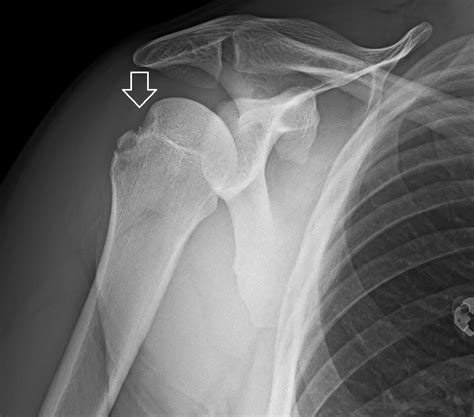

Experiencing a sudden, sharp pain in your shoulder after a fall or a sports-related impact is a distressing ordeal. Often, the first thing medical professionals will order to assess the situation is a Dislocated Shoulder X Ray. Understanding why this imaging is critical, what it reveals, and how it guides your recovery journey is essential for anyone dealing with this common orthopedic injury. A dislocated shoulder occurs when the ball of your upper arm bone (the humerus) pops out of the shoulder socket (the glenoid). Because this area is complex, precise imaging is the gold standard for confirming the diagnosis and ruling out associated complications.

• Visualizing the position of the bones: It confirms whether the humerus is truly out of the socket or if there is a partial dislocation (subluxation).

• Assessing alignment: It helps doctors identify the specific type of dislocation—whether it is anterior (forward), posterior (backward), or inferior (downward).

• Anteroposterior (AP) View: Taken from the front, this view helps doctors see the general relationship between the humerus and the socket.

Hill-Sachs Lesion A small indentation or "dent" on the back of the humeral head, often caused by the bone hitting the rim of the socket during dislocation.